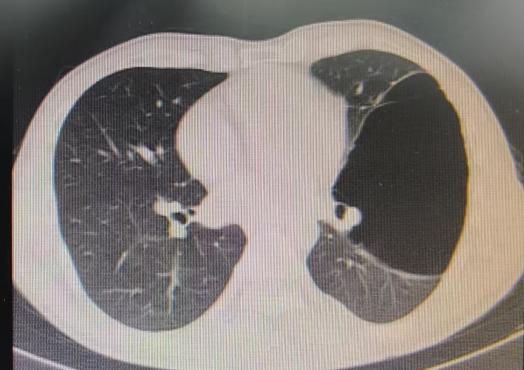

近期,国内知名呼吸介入专家陈愉教授联合做爱自拍 呼吸与危重症医学科团队,为李先生施行“胸腔镜下肺大疱探查术 + 胸腔闭式引流术”。手术中,陈愉教授运用单孔胸腔镜技术,仅在患者胸壁开了一个1cm的小切口。通过高清胸腔镜系统探查发现,患者胸腔内存在广泛粘连以及多发微小肺大疱,肺叶解剖结构异常,肺门血管直接暴露,经判断肺大疱腔已与胸腔贯通。

面对这一复杂状况,陈教授凭借丰富的经验果断调整手术方案。在确保安全的前提下,对可疑病灶进行了精准活检取样,随后精准置入胸腔引流管。术后即刻CT确认引流管位置良好,同时制定了严密的术后管理方案:每日监测引流量及肺复张情况,若引流量持续减少且肺大疱逐渐缩小,则按计划拨管;若肺大疱未明显缩小,则考虑拔除引流管后转外科进行胸膜剥离术。

术后复查CT显示,肺大疱明显缩小,患者胸闷症状显著减轻。整个手术过程进展顺利,患者术后恢复良好。

(术前左肺肺大疱明显-术后肺大疱逐渐缩小闭合)